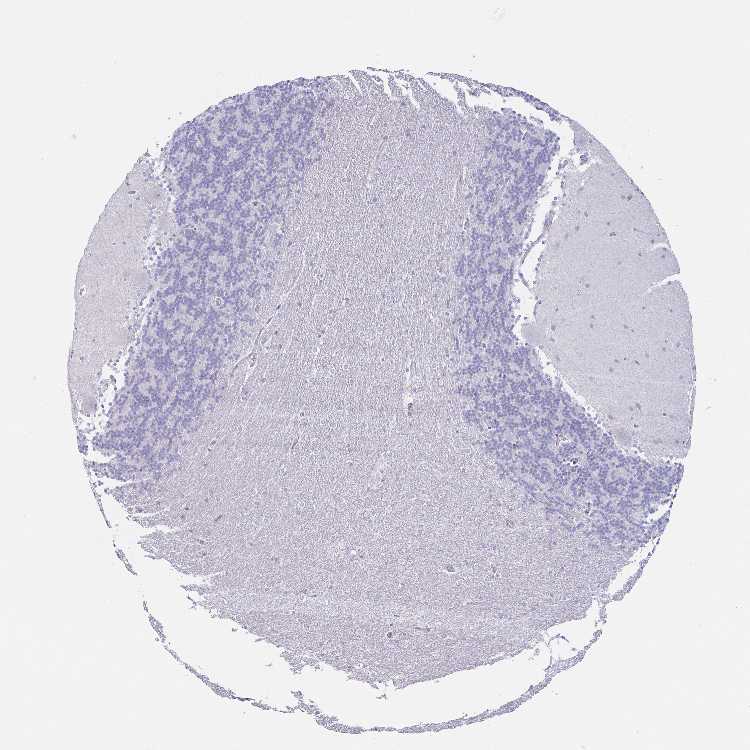

CEREBELLUM - Antibody stainingi

Antibody staining in the annotated cell types in the current human tissue is reported as not detected, low, medium, or high, based on conventional immunohistochemistry profiling in selected tissues. This score is based on the combination of the staining intensity and fraction of stained cells.

Each image is clickable and will lead to virtual microscopy that enables deeper exploration of all samples and also displays staining intensity scores, fraction scores and subcellular localization as well as patient and tissue information for each sample.

Antibody HPA054577

Purkinje cells Not detected

Cells in granular layer Not detected

Cells in molecular layer Not detected